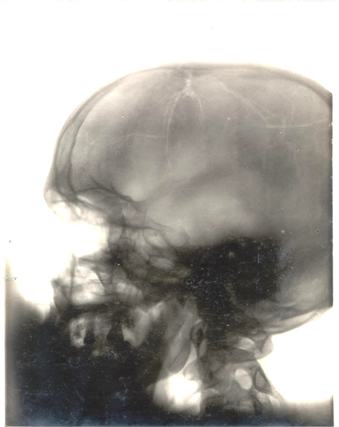

Άλλα αντικείμενα που δημοπρατήθηκαν ήταν μία ακτινογραφία του εγκεφάλου του Αϊνστάιν για 38,750 δολάρια, και μπουκαλάκια από τα συνταγογραφημένα φάρμακα της Μέριλιν Μονρόε για 18,750 δολάρια. Η δημοπρασία συγκέντρωσε συνολικά 3 εκατομμύρια δολάρια.